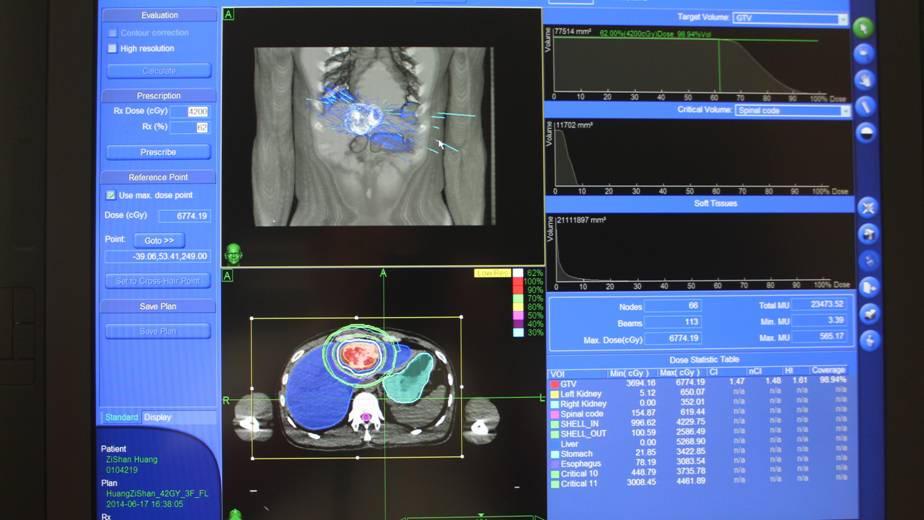

“除了照射时没胃口吃东西,别的没有不舒服。”黄先生对治疗过程很满意。治疗后他的症状已消失,在6月24日已带中药出院回家。以下是射波刀治疗的剂量数据和剂量曲线。

射波刀剂量数据和剂量曲线